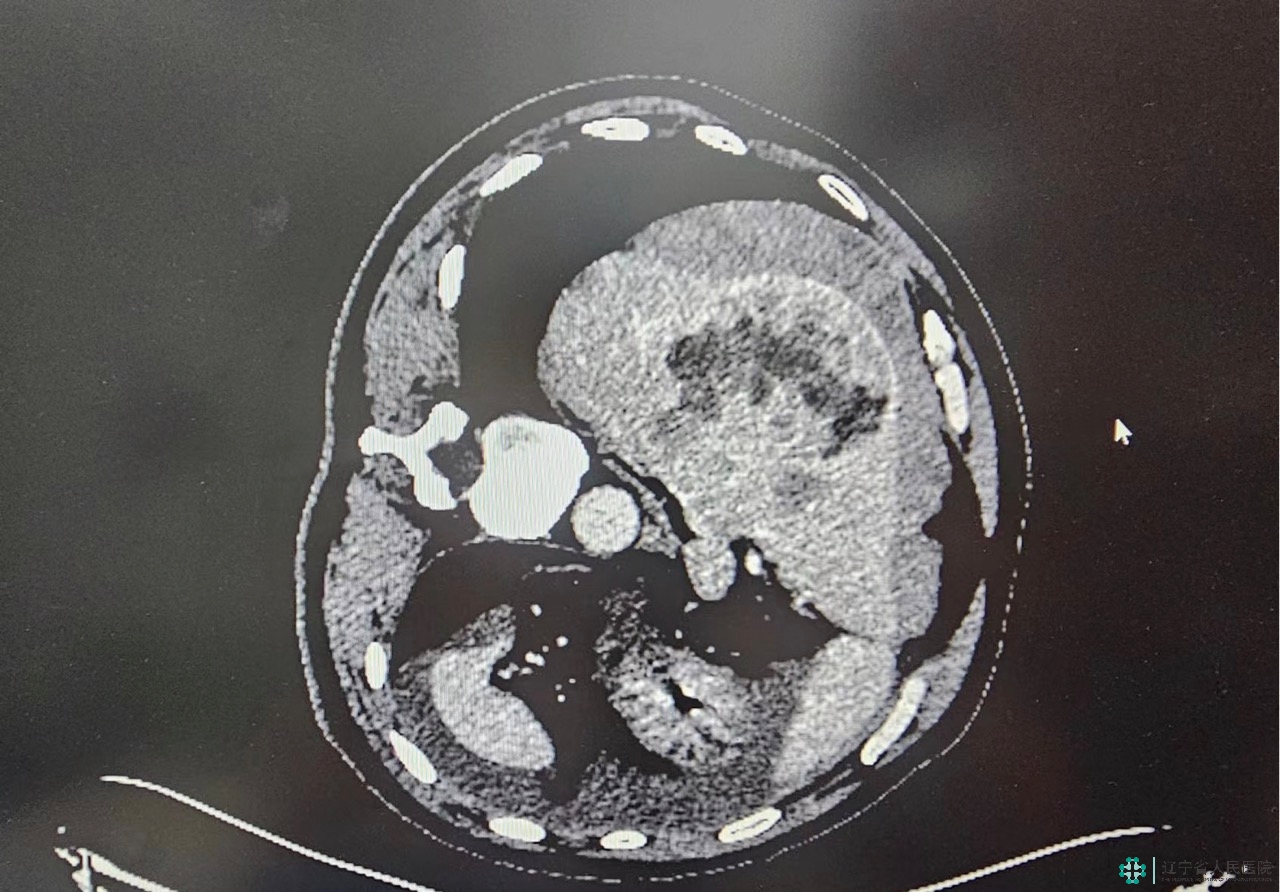

我院多学科联动成功救治突发肝癌破裂出血的外地游客

家人迅速拨打120,将患者转运到我院急诊医学科。急诊医学科胡晓主任、主任医师赵俊伟快速开辟抢救绿色通道,普外科专家、副院长卜献民凭借多年的临床经验,迅速诊断其为肝癌破裂出血。

原来患者患有乙肝20余年,近两年来 ,一直抽血化验检测,但并未行超声及CT等影像检查,患者及家属对肝癌的病情毫不知情。身处异地,突如其来的肝癌破裂出血急症,以及肝癌的诊断,给患者一家带来了沉重的打击,全院多学科救治,一场挽救生命的与时间赛跑就此开始。

因患者处于休克代偿期,外周静脉血管干瘪,血管入路十分困难,护理团队凭借精湛的技术,迅速建立通路;患者腹痛剧烈,强迫体位,不能平卧,麻醉科给予局麻强化辅助,患者完成配合体位,介入医学科副主任(主持工作)周玉斌及其团队快速精准的找到了出血责任动脉和病灶,并迅速进行精准栓塞;术中,麻醉科及输血科为患者的生命同时保驾护航……经过了1个多小时的手术,我院医疗团队,成功挽救患者生命,使患者转危为安。